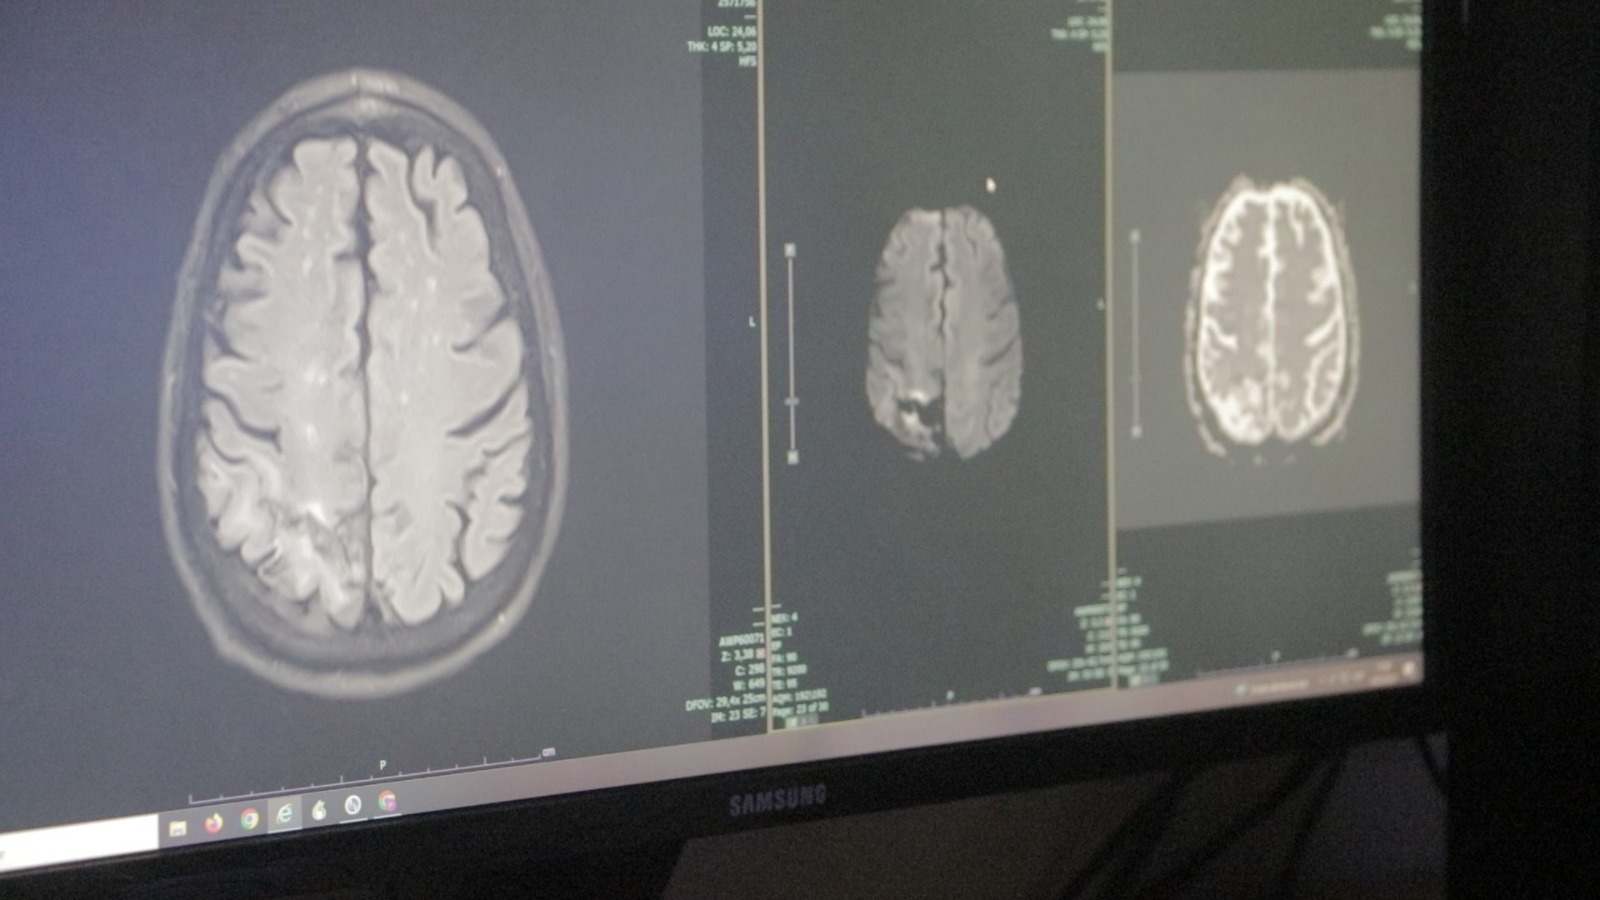

El accidente cerebrovascular (ACV) en muchos casos puede presentar signos de advertencia. Entre los factores de riesgo más comunes se encuentran la hipertensión, la obesidad, la diabetes, el colesterol elevado y el tabaquismo. El ACV se divide en dos tipos principales: el isquémico, que ocurre por obstrucción de los vasos sanguíneos, y el hemorrágico, que se produce por sangrado dentro del cerebro.

El Dr. Carlos Barros MPO4700 MN143746, a cargo del Servicio de Neurología del Hospital Madariaga, explicó que “el ACV es una patología que puede ser de forma isquémica o hemorrágica, siendo esta última menos frecuente”.